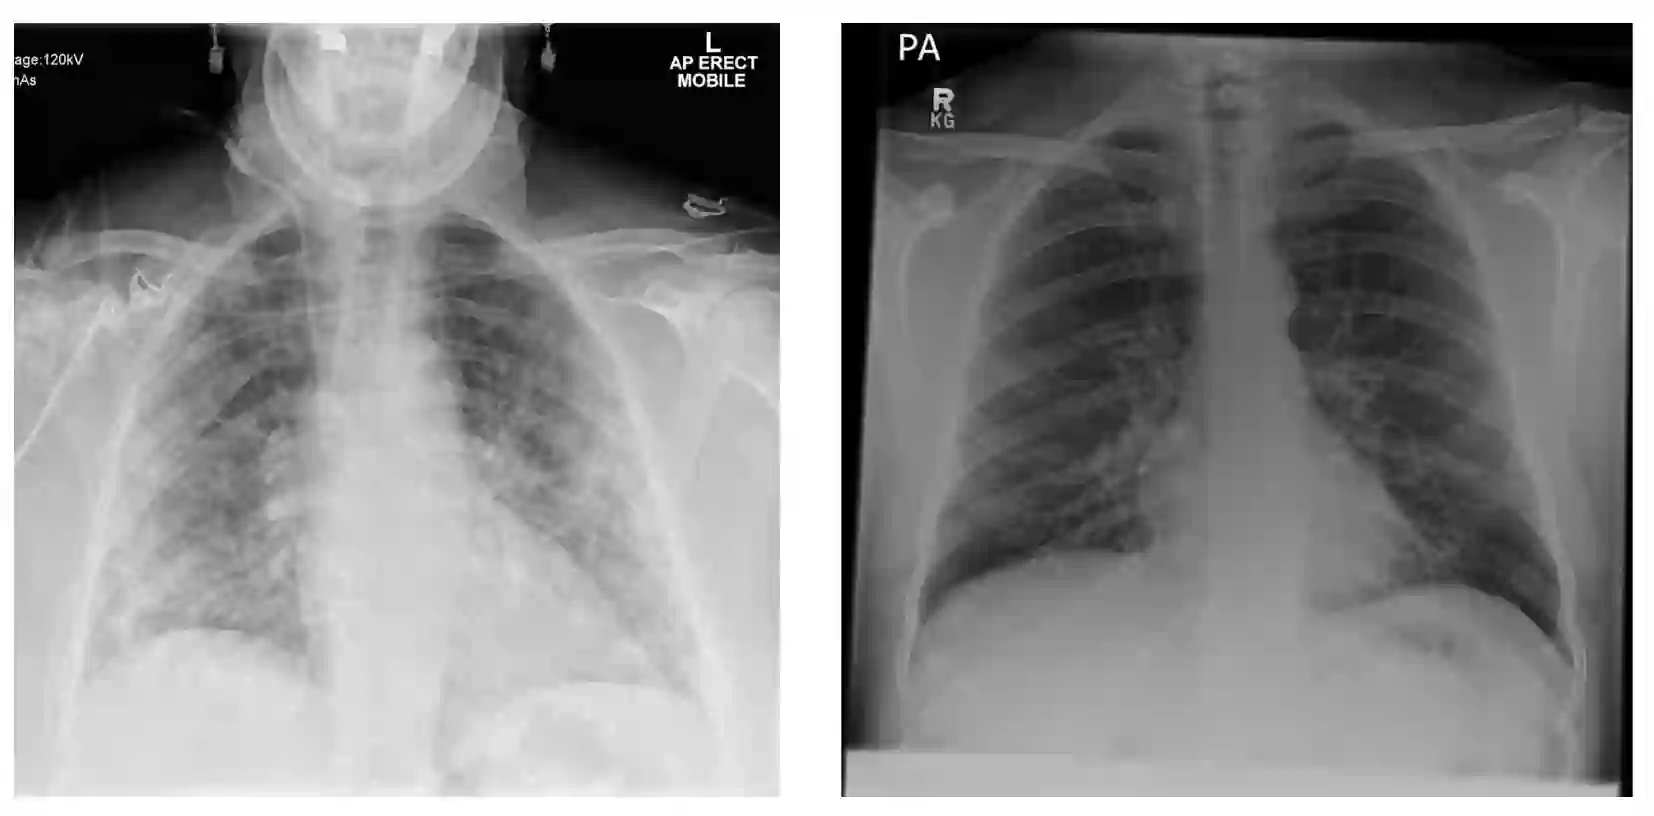

During the COVID-19 pandemic, the sheer volume of imaging performed in an emergency setting for COVID-19 diagnosis has resulted in a wide variability of clinical CXR acquisitions. This variation is seen in the CXR projections used, image annotations added and in the inspiratory effort and degree of rotation of clinical images. The image analysis community has attempted to ease the burden on overstretched radiology departments during the pandemic by developing automated COVID-19 diagnostic algorithms, the input for which has been CXR imaging. Large publicly available CXR datasets have been leveraged to improve deep learning algorithms for COVID-19 diagnosis. Yet the variable quality of clinically-acquired CXRs within publicly available datasets could have a profound effect on algorithm performance. COVID-19 diagnosis may be inferred by an algorithm from non-anatomical features on an image such as image labels. These imaging shortcuts may be dataset-specific and limit the generalisability of AI systems. Understanding and correcting key potential biases in CXR images is therefore an essential first step prior to CXR image analysis. In this study, we propose a simple and effective step-wise approach to pre-processing a COVID-19 chest X-ray dataset to remove undesired biases. We perform ablation studies to show the impact of each individual step. The results suggest that using our proposed pipeline could increase accuracy of the baseline COVID-19 detection algorithm by up to 13%.